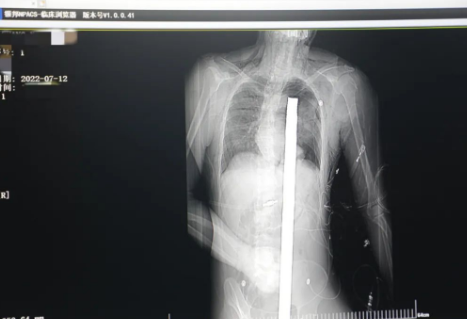

時(shí)間就是生命!此時(shí),西安國(guó)際醫(yī)學(xué)中心醫(yī)院展開了一場(chǎng)與生命賽跑的搶救,第一時(shí)間開辟綠色通道,急診X光片及CT顯示:異物經(jīng)會(huì)陰部貫穿盆腔、腹腔到達(dá)左側(cè)胸腔主動(dòng)脈弓水平。醫(yī)院創(chuàng)傷中心立即啟動(dòng)應(yīng)急預(yù)案,劉延彤副院長(zhǎng)親臨指揮,下午17點(diǎn)48分,當(dāng)患者被送達(dá)手術(shù)室,胸外、心外、肝膽外科、胃腸外科,泌尿外科及麻醉科等多學(xué)科專家聯(lián)手對(duì)這名工友進(jìn)行“縱劈胸骨 前外側(cè)開胸探查 氣管及主支氣管修補(bǔ) 肺修補(bǔ) 血胸清除 開腹探查止血 腹膜后及盆腔探查......”手術(shù)。

情況緊急!術(shù)中探查后發(fā)現(xiàn),長(zhǎng)120cm直徑3cm的螺紋鋼經(jīng)患者右側(cè)會(huì)陰部穿入,傷及直腸,途徑膀胱后方,左側(cè)髂總動(dòng)靜脈之間傷及左腎后,經(jīng)胰腺后方在肝脾之間穿破膈肌,在下肺靜脈前方穿入左肺穿破氣管及左右主支氣管膜部,止于主動(dòng)脈弓下水平,穿入體內(nèi)的部分達(dá)到75cm。